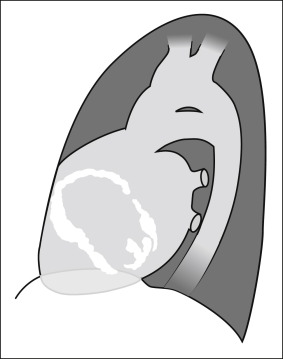

Pericardial calcification ( Figs. 27-1 to 27-4 ) is most prominent in the interventricular and atrioventricular grooves, and lateral to the right atrial and ventricular walls ( Graphic 27-1 ). When looking for pericardial calcification, it is necessary to scrutinize the lateral chest radiograph well, particularly the diaphragmatic surface. Pericardial calcification does not usually involve the left heart as much the right heart, and it does not often involve the apex (which, if calcified, is far more often due to prior infarction). Pericardial calcification should prompt serious consideration of the diagnosis of constrictive pericarditis, and clinicians should seek other radiographic and clinical features of constriction.